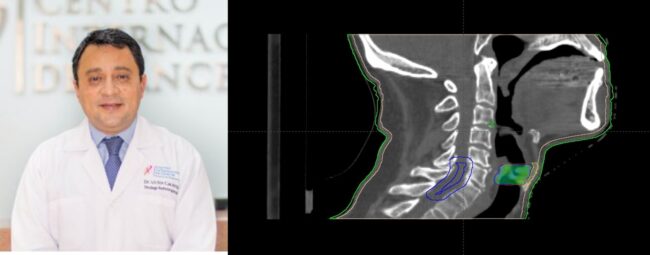

El paciente acudió en el año 2019 con disfonía y dolor de 4 meses de duración. Se le diagnosticó un Cáncer de células escamosas en la cuerda vocal derecha. Se consideró una etapa intermedia, ya que afectaba la cuerda vocal casi paralizándola.

Fue tratado en nuestro centro con un esquema de radioterapia convencional de 35 sesiones, y rápidamente se recuperó hasta quedar sin evidencia de enfermedad. En este primer tratamiento recibió esta dosis de radiación de forma integral en toda la laringe ya que este es el protocolo estándar con estos pacientes. Se vigiló durante dos años.